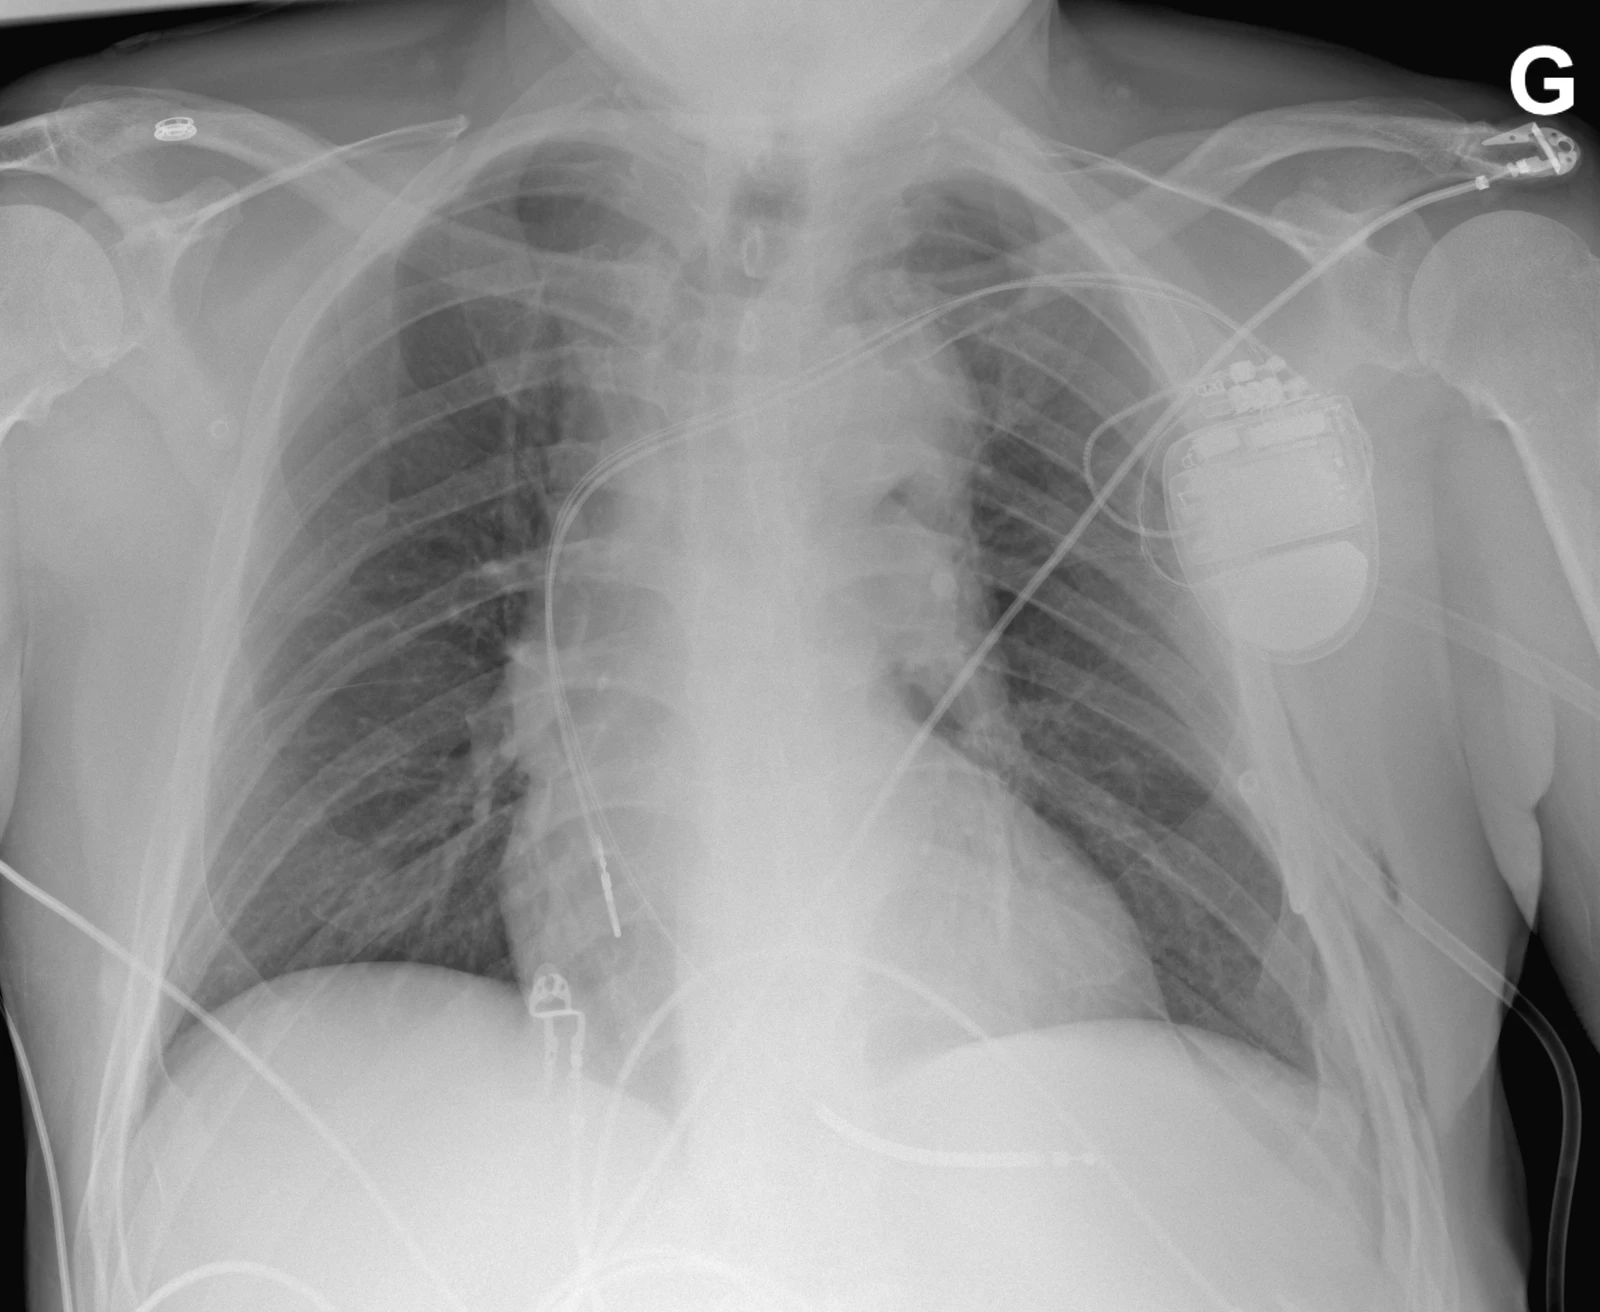

Cette radiographie a été prise chez le même patient après la pose d’un drain thoracique à gauche et montre une disparition radiologique du pneumothorax.

A noter qu’on utilisera si possible un drain de petit calibre (≤ 14 Fr). La voie antérieure (ligne médioclaviculaire) utilisée pour exsuffler un pneumothorax en urgence peu également être utilisée pour poser un drain (de préférence de petit calibre), offrant l’avantage de poser le drain à l’endroit où se trouve l’air. En cas de pose de PM récente, ce dernier peut gêner l’abord antérieur.